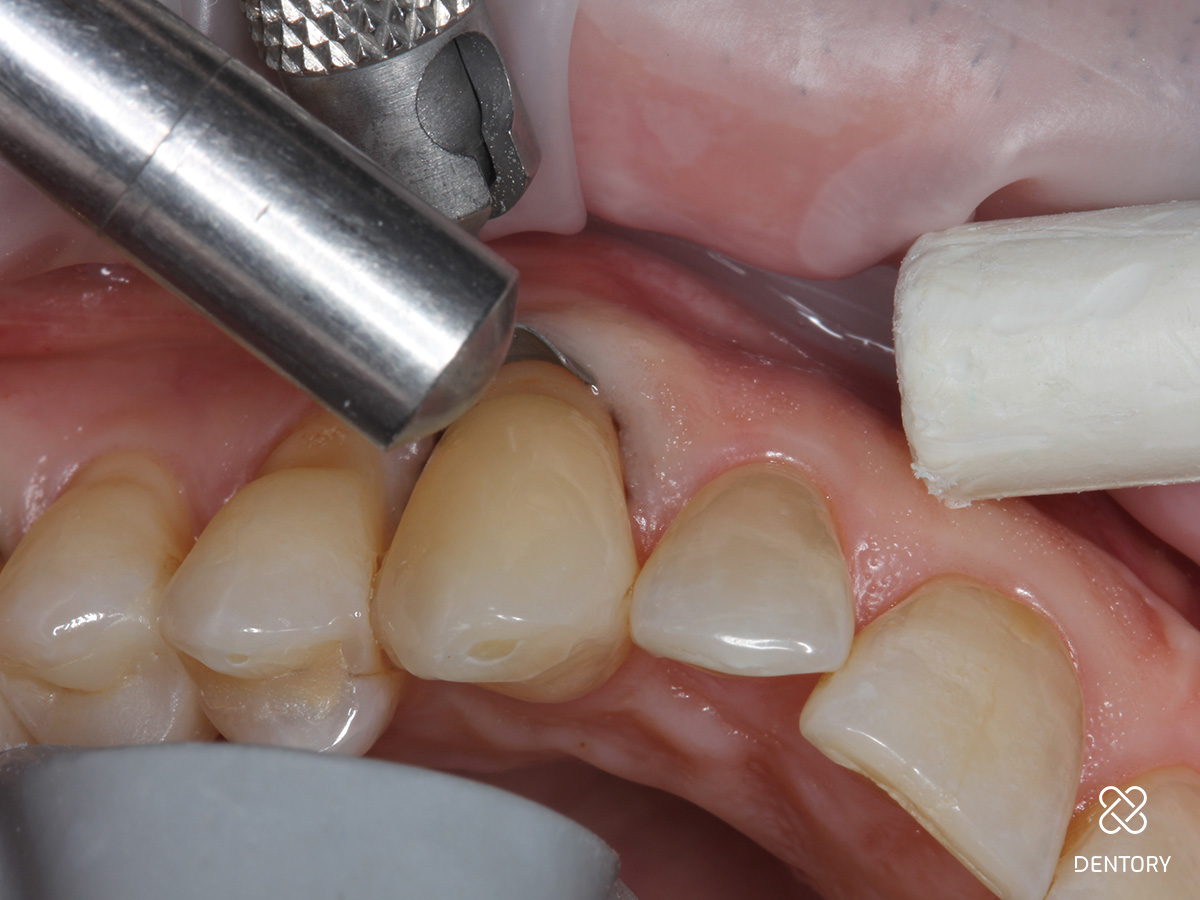

Abbildung 2

Beurteilung der Lage der Kavität nach zervikal. Liegt der Defekt supragingival, kann auf den Sulkus-Faden verzichtet werden. Liegt der Defekt äquigingival oder subgingival wird ein 00-Faden gelegt.